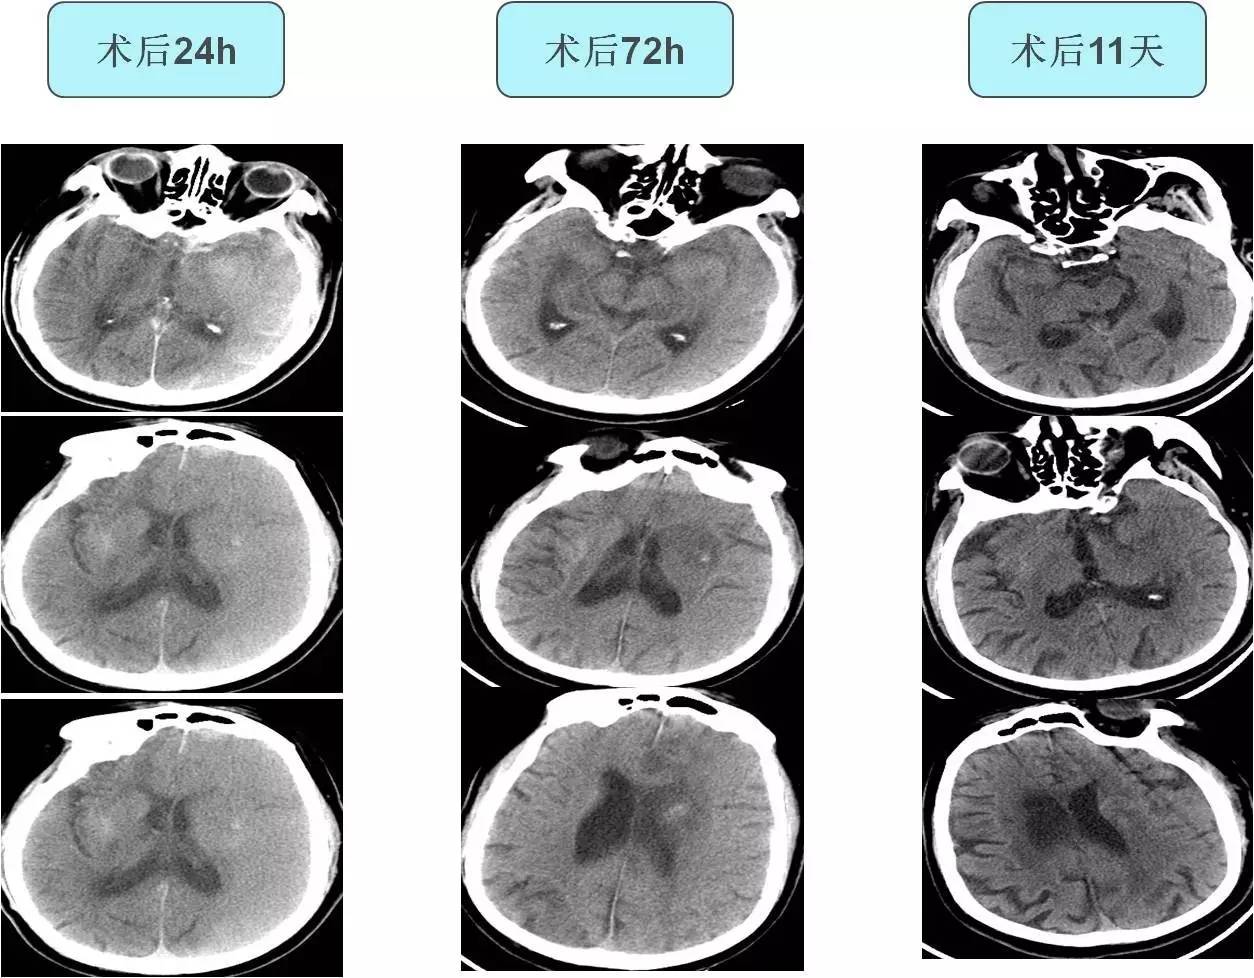

不同时间CT表现

#头颅CT:传统头部CT通常对于早期识别CHS帮助很小,头部CT提示弥漫性或片状白质水肿、占位效应或术侧颅内出血可能与CHS有关。